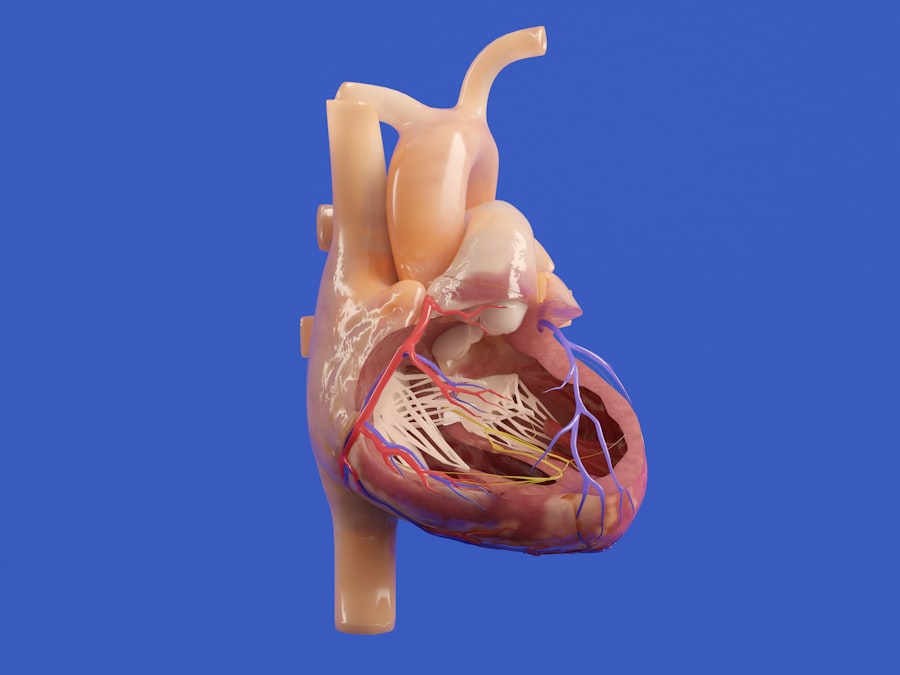

In threat mode, your body undergoes a series of changes that prepare you for action. Your heart rate increases, breathing becomes more rapid, and blood flow is redirected to essential muscles. This response is not merely a physical reaction; it also involves cognitive processes that heighten your awareness and focus.

The autonomic nervous system (ANS) is a critical component of your overall nervous system that regulates involuntary bodily functions such as heart rate, digestion, and respiratory rate. It operates largely below the level of consciousness, allowing you to focus on other tasks while still maintaining essential bodily functions. The ANS is divided into two main branches: the sympathetic nervous system (SNS) and the parasympathetic nervous system (PNS).

The SNS is responsible for activating the fight or flight response during times of stress, while the PNS promotes relaxation and recovery. When you find yourself in a threatening situation, the sympathetic branch of your ANS kicks into gear, preparing your body for action. Conversely, once the threat has passed, the parasympathetic branch helps restore balance by calming your body down and returning it to a state of rest.

| Heart Rate (bpm) | Number of heartbeats per minute | 60-100 (resting), 100-140 (threat response) | Increases during threat mode to prepare body for fight or flight |

| Respiratory Rate (breaths/min) | Number of breaths per minute | 12-20 (resting), 20-40 (threat response) | Elevated to increase oxygen intake during threat response |

| Pupil Dilation | Diameter of pupils | Normal (rest), Dilated (threat mode) | Increases visual acuity during threat response |

| Muscle Tension | Level of muscle contraction | Low (rest), High (threat mode) | Prepares muscles for rapid action in threat situations |

Your emotional responses are intricately linked to the functioning of your nervous system. When you experience emotions such as fear or anxiety, these feelings are not just abstract concepts; they manifest physically within your body through various physiological changes driven by your nervous system. For example, when you’re anxious about an upcoming presentation, you may notice an increased heart rate or shallow breathing—both signs that your nervous system is reacting to perceived stress.

During threat mode activation, heart rate and blood pressure increase, pupils dilate, breathing becomes rapid, and blood flow is redirected to muscles. These changes prepare the body to respond quickly to danger.